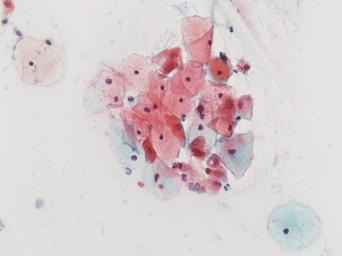

Keywords: lesión intraepitelial escamosa de bajo grado lesiónintraepitelialescamosadebajogrado citología de cuello uterino citologíadecuellouterino citología exfoliativa ginecológica citologíaexfoliativaginecológica citología de cribado citologíadecribado citología anatomía patológica anatomíapatológica bethesda 2001 bethesda2001 osuna cérvix uterino cérvixuterino hpv españa screening lsil enfermedades de transmisión sexual enfermedadesdetransmisiónsexual imágenes de citología ginecológica imágenesdecitologíaginecológica papanicolaou test de papanicolaou testdepapanicolaou tinción de papanicolaou tincióndepapanicolaou Células con núcleo y citoplasma aumentado de tamaño, núcleos irregulares, como plumosos, tendencia al color naranja de muchas células, halos en algunos casos, núcleos dobles en otros, algunos núcleos hipercromáticos. Células con núcleo y citoplasma aumentado de tamaño, núcleos irregulares, como plumosos, tendencia al color naranja de muchas células, halos en algunos casos, núcleos dobles en otros, algunos núcleos hipercromáticos. |